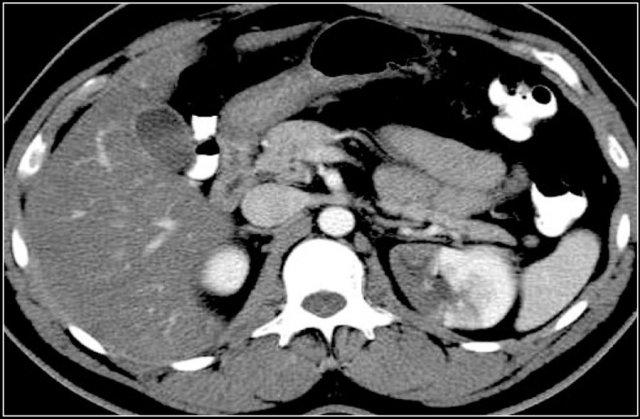

Trong trường hợp này, có các vùng giảm tỷ trọng ở cả hai thận.

Chỉ dựa trên hình ảnh, chẩn đoán phân biệt chính bao gồm viêm bể thận đa ổ, u lympho và di căn.

Bệnh nhân này có tiền sử nhiễm trùng đường tiết niệu, các đợt đau hông lưng và không có tiền sử u nguyên phát hay u lympho.

Do đó, chẩn đoán là viêm bể thận.

Chụp CT 4 tháng sau cho thấy sự ngấm thuốc bình thường của cả hai thận; các bất thường thận trên lần chụp đầu tiên do đó phù hợp với một đợt viêm bể thận đa ổ.